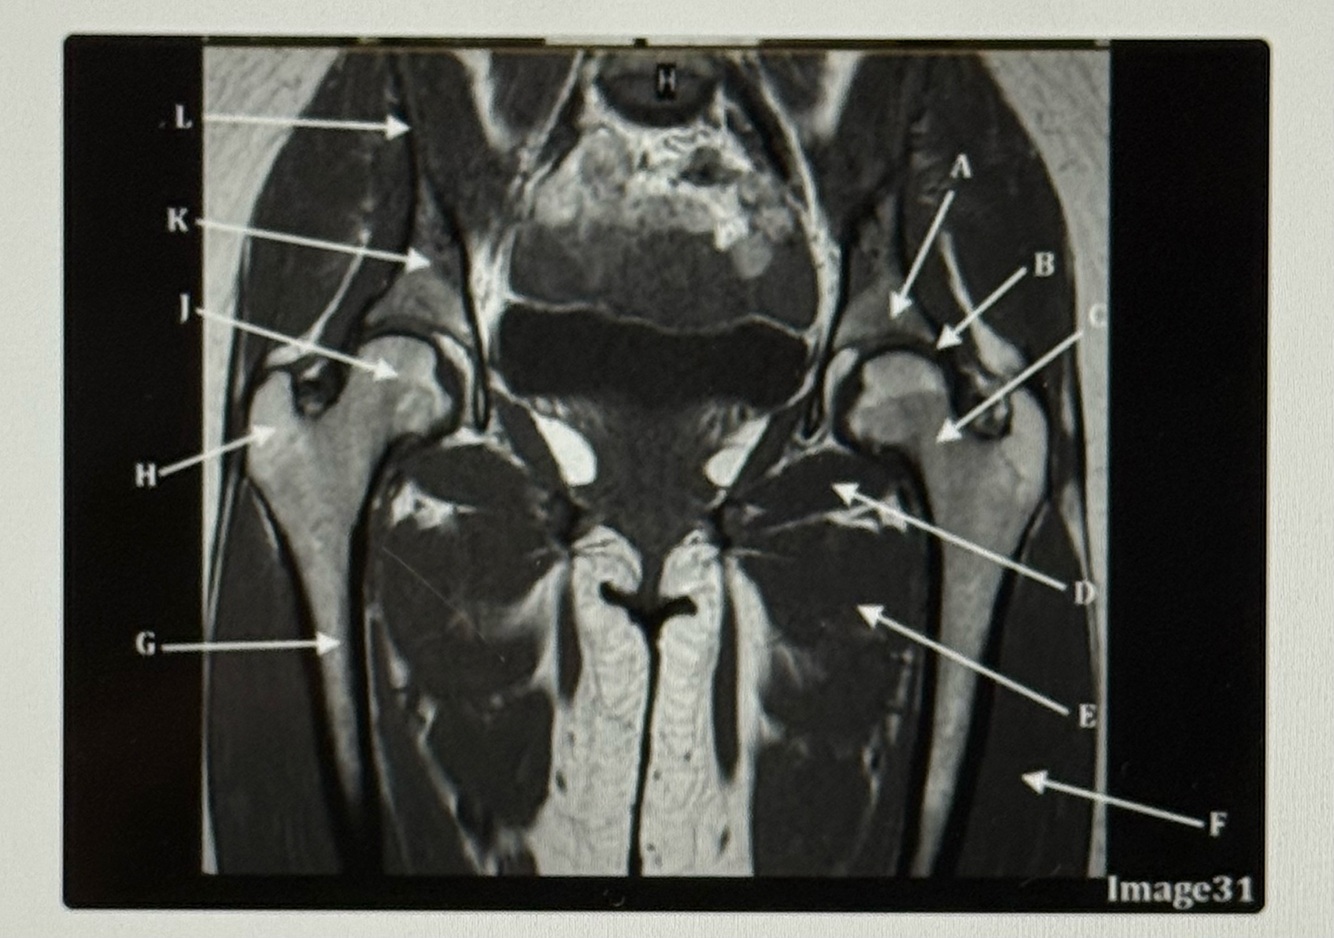

Letter A is pointing to the

Bladder

Letter B is pointing to the

Labrum

Letter A points to the

Acetabulum

Letter B points to the

Letter C points to the

Femoral neck

Letter D points to the

Obturator externus

Letter E points to the

Adductor muscles

Letter F points to the

Vastus lateralis

Letter G points to the

Femur

Letter H is pointing to the

Greater trochanter

Letter J points to the

Femoral head

Letter K points to the

Body of the ilium

Letter L points to the